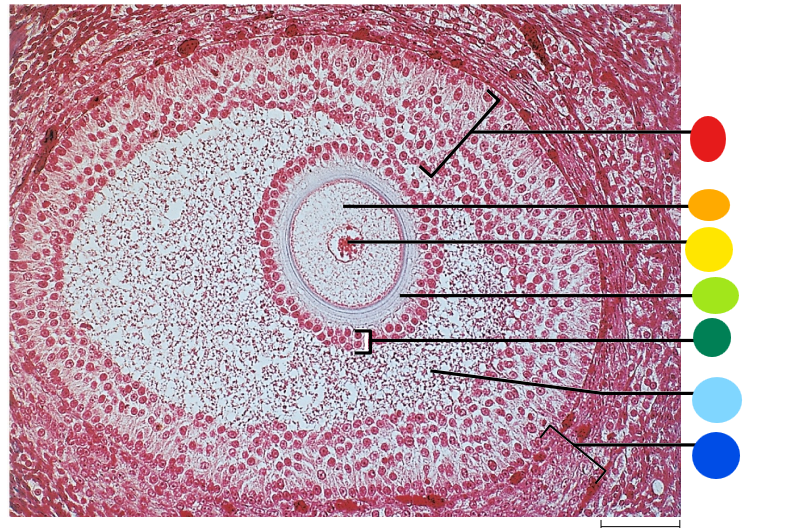

red

granulosa cells

orange

primary or secondary oocyte

yellow

oocyte nucleus

light green

zona pellucida

dark green

cumulus oophorus

light blue

antrum

dark blue

thecal cells

what is this

tertiary follicle